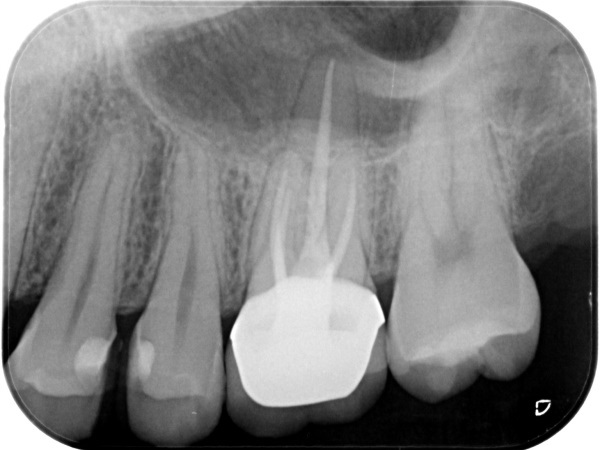

根管治療終了後3か月経過